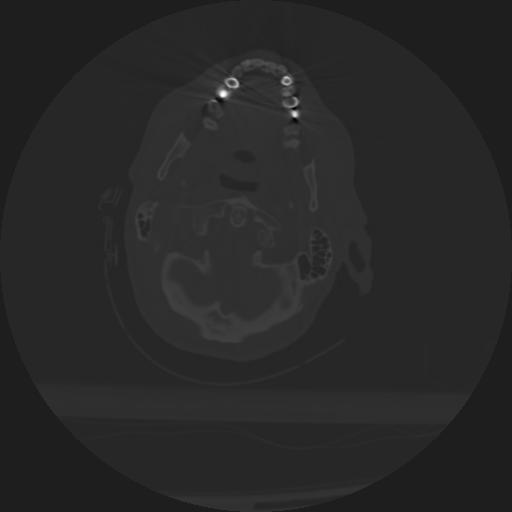

22 ANGIO,CE,Vol,0.5,ANGIO,,